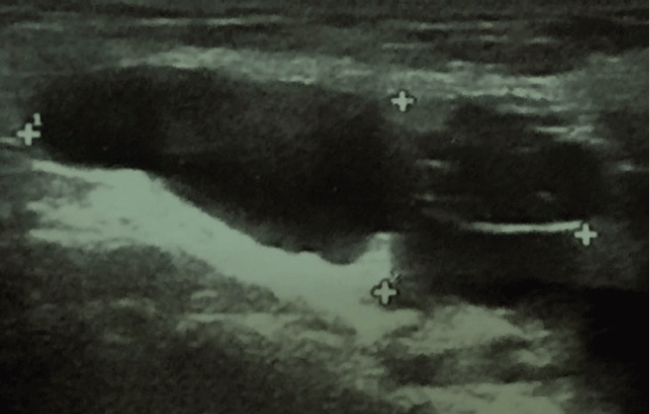

A 38-year-old woman presented to our Institution for a suspicious right sliding inguinal hernia. She had complained of reducible swelling in her right groin for about three years. She noticed a slight increase in the size of the swelling after childbirth. There was no history of abdominal pain or bowel dysfunction. The palpable mass could be repositioned manually and became clinically evident only three months before our clinical examination. Ultrasonographic examination by linear probe revealed the mass to be hypoechoic and homogeneous without solid components. Color Doppler was negative and it measured 13 × 36 mm at inguinal ultrasound. The lesion appeared to be in contact with the right ovary connected at its base with the parietal peritoneum as detected by successive transvaginal examination (Figure 2 and Figure 3). MRI showed Sagittal T2-weighted MR image linked to a fluid-intensity tumor led to the inguinal canal. Enhanced T2-weighted MRI revealed no solid component within the cystic tumor in contact with the ovary.

Figure 3 Dimension reported in right inguinal canal lesion in patient 2 (13 × 36 mm).